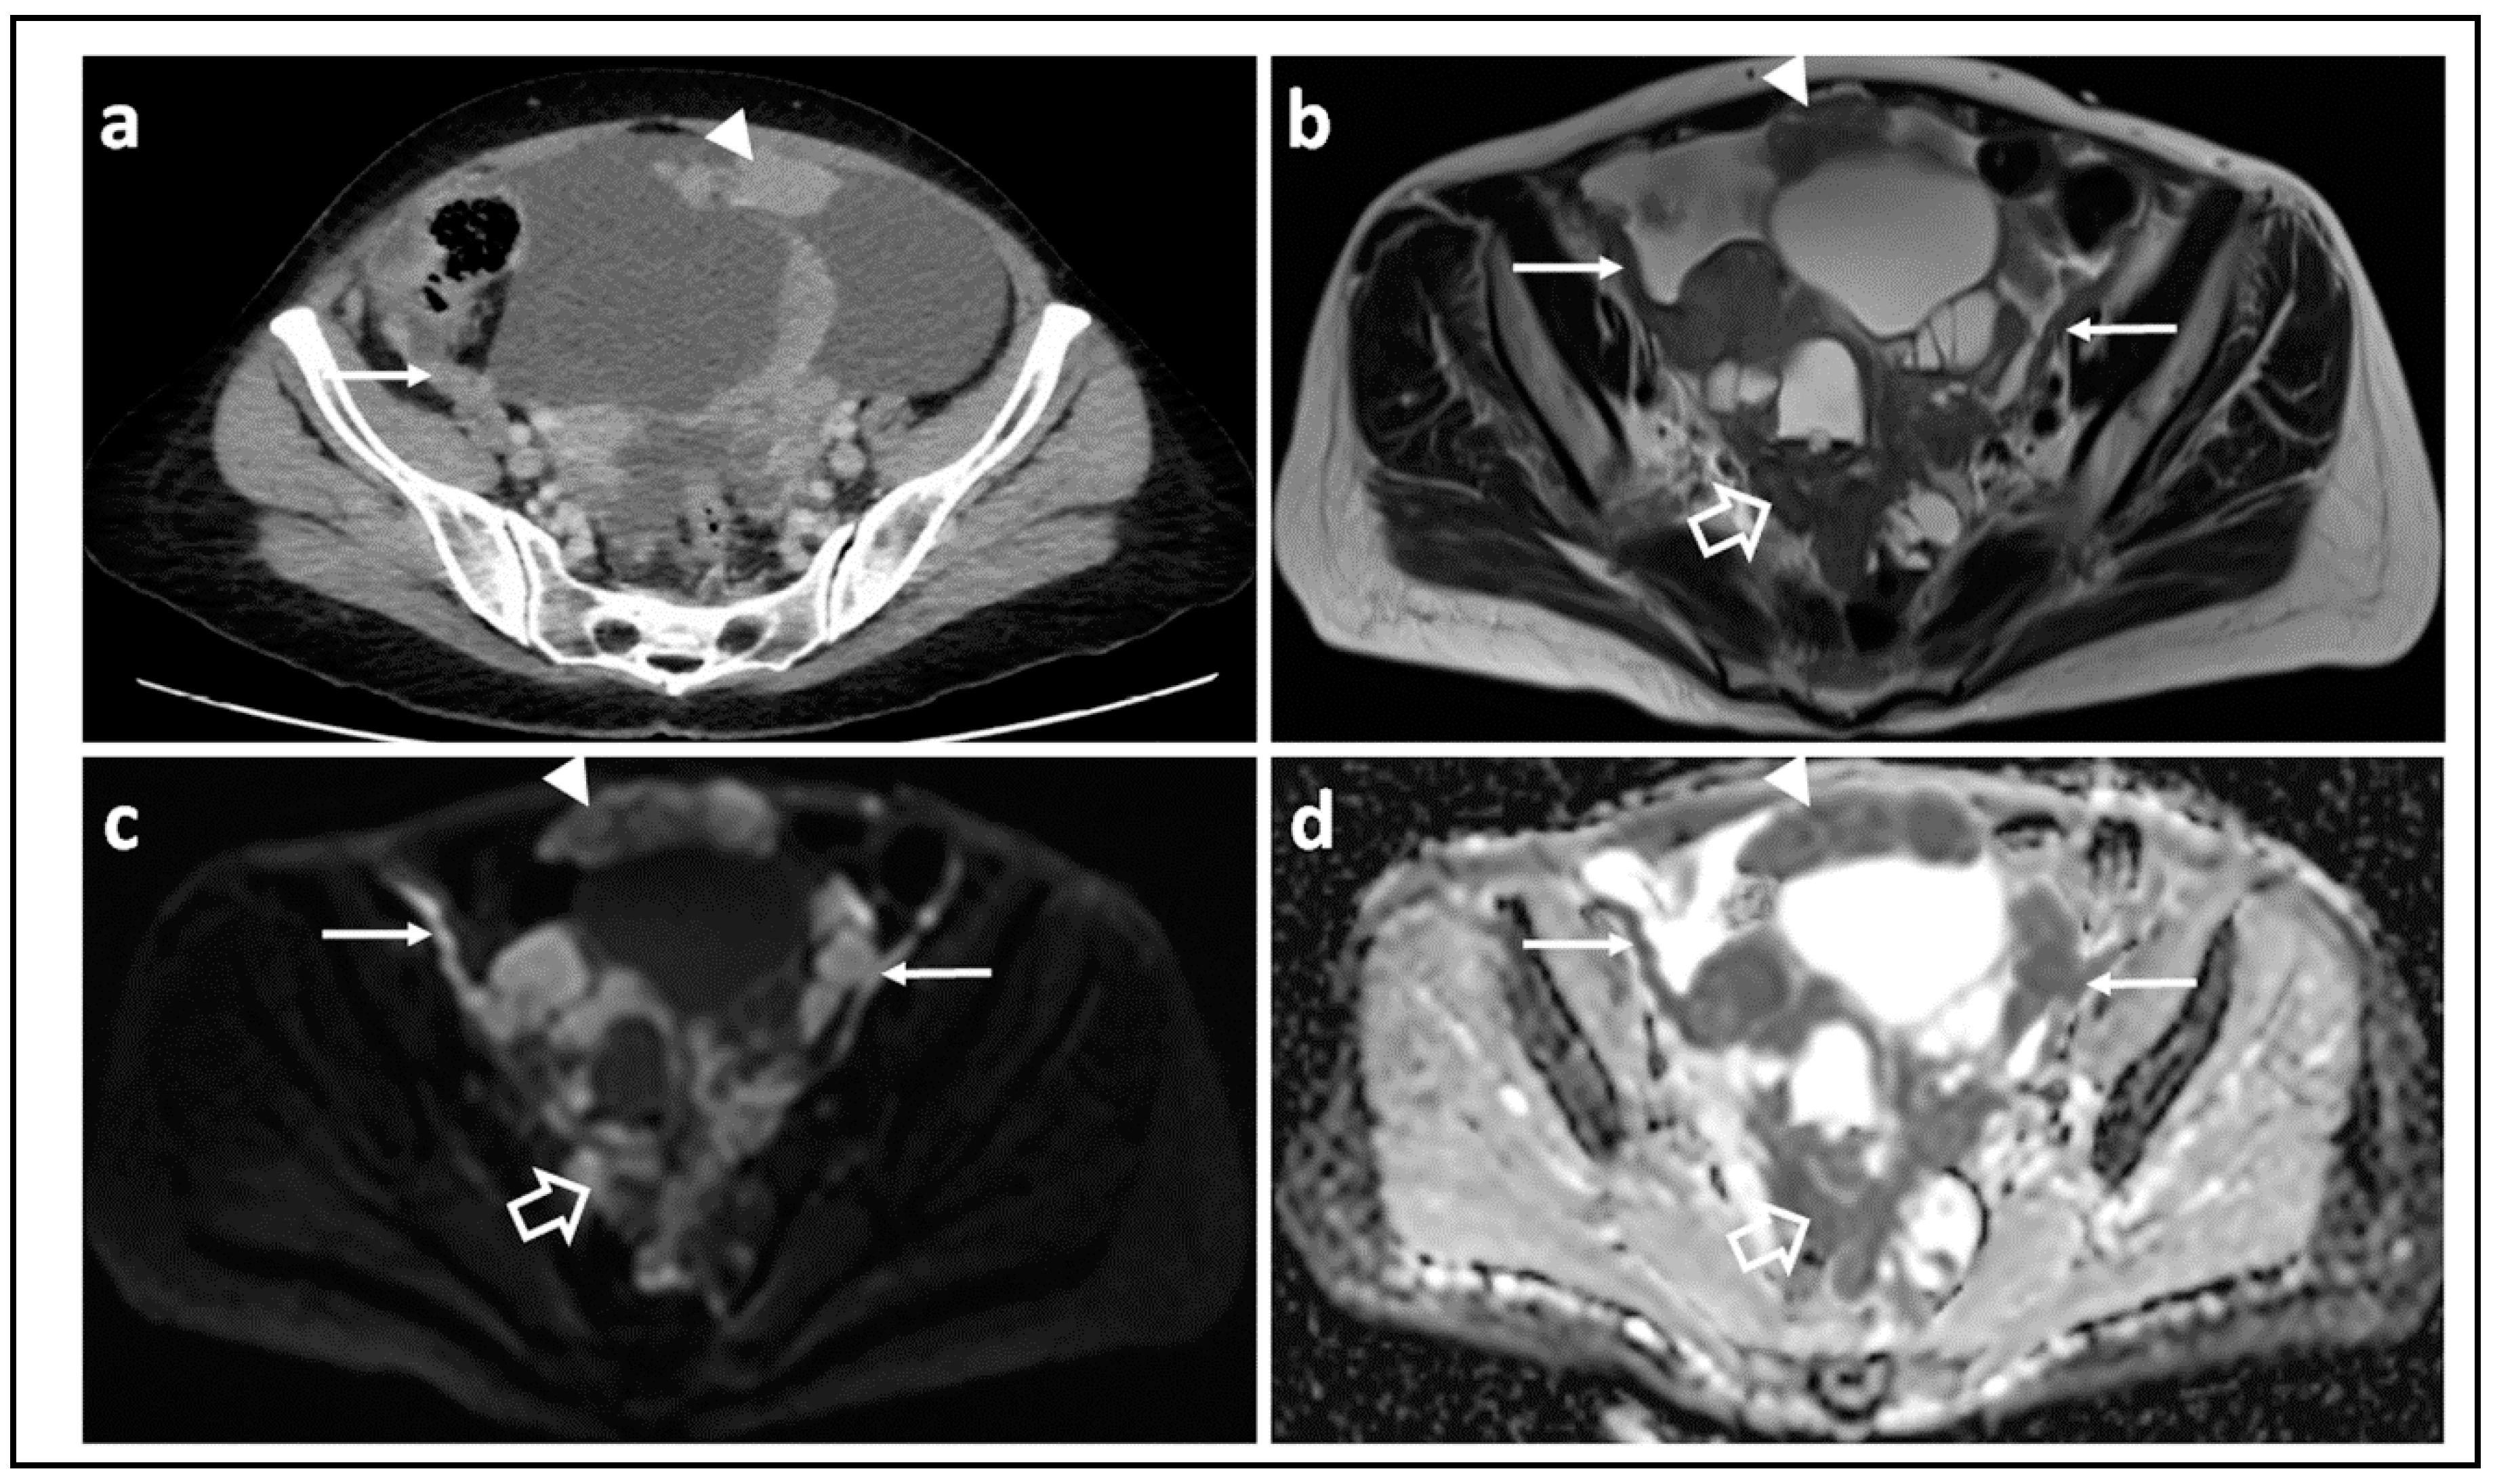

- Prado, J.G.; Hernando, C.G.; Delgado, D.V.; Martínez, R.S.; Bhosale, P.; Sanchez, J.B.; Chiva, L. Diffusion-weighted magnetic resonance imaging in peritoneal carcinomatosis from suspected ovarian cancer: Diagnostic performance in correlation with surgical findings. Eur. J. Radiol. 2019, 121, 108696. [Google Scholar] [CrossRef]

- Rizzo, S.; De Piano, F.; Buscarino, V.; Pagan, E.; Bagnardi, V.; Zanagnolo, V.; Colombo, N.; Maggioni, A.; Del Grande, M.; Del Grande, F.; et al. Pre-operative evaluation of epithelial ovarian cancer patients: Role of whole body diffusion weighted imaging MR and CT scans in the selection of patients suitable for primary debulking surgery. A single-centre study. Eur. J. Radiol. 2020, 123, 108786. [Google Scholar] [CrossRef]

- Michielsen, K.; Vergote, I.; De Beeck, K.O.; Amant, F.; Leunen, K.; Moerman, P.; Deroose, C.; Souverijns, G.; Dymarkowski, S.; De Keyzer, F.; et al. Whole-body MRI with diffusion-weighted sequence for staging of patients with suspected ovarian cancer: A clinical feasibility study in comparison to CT and FDG-PET/CT. Eur. Radiol. 2013, 24, 889–901. [Google Scholar] [CrossRef]

- Michielsen, K.; Dresen, R.; Vanslembrouck, R.; De Keyzer, F.; Amant, F.; Mussen, E.; Leunen, K.; Berteloot, P.; Moerman, P.; Vergote, I.; et al. Diagnostic value of whole body diffusion-weighted MRI compared to computed tomography for pre-operative assessment of patients suspected for ovarian cancer. Eur. J. Cancer 2017, 83, 88–98. [Google Scholar] [CrossRef]

- Engbersen, M.; Sant, I.V.T.; Lok, C.; Lambregts, D.; Sonke, G.; Beets-Tan, R.; van Driel, W.; Lahaye, M. MRI with diffusion-weighted imaging to predict feasibility of complete cytoreduction with the peritoneal cancer index (PCI) in advanced stage ovarian cancer patients. Eur. J. Radiol. 2019, 114, 146–151. [Google Scholar] [CrossRef]